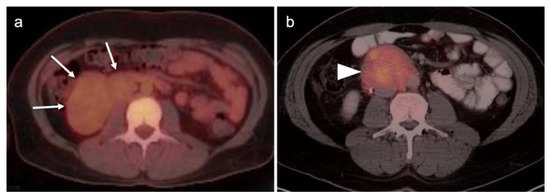

2.2. Ovarian Epithelial, Fallopian Tube and Primary Peritoneal Carcinoma